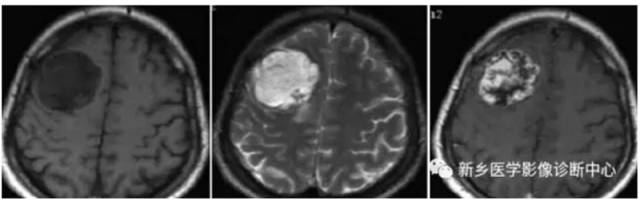

3、MRI :T2WI 呈稍高信号, T1WI 呈稍低信号, 明显增强而均匀强化; 部分病例可见明显的瘤周水肿。